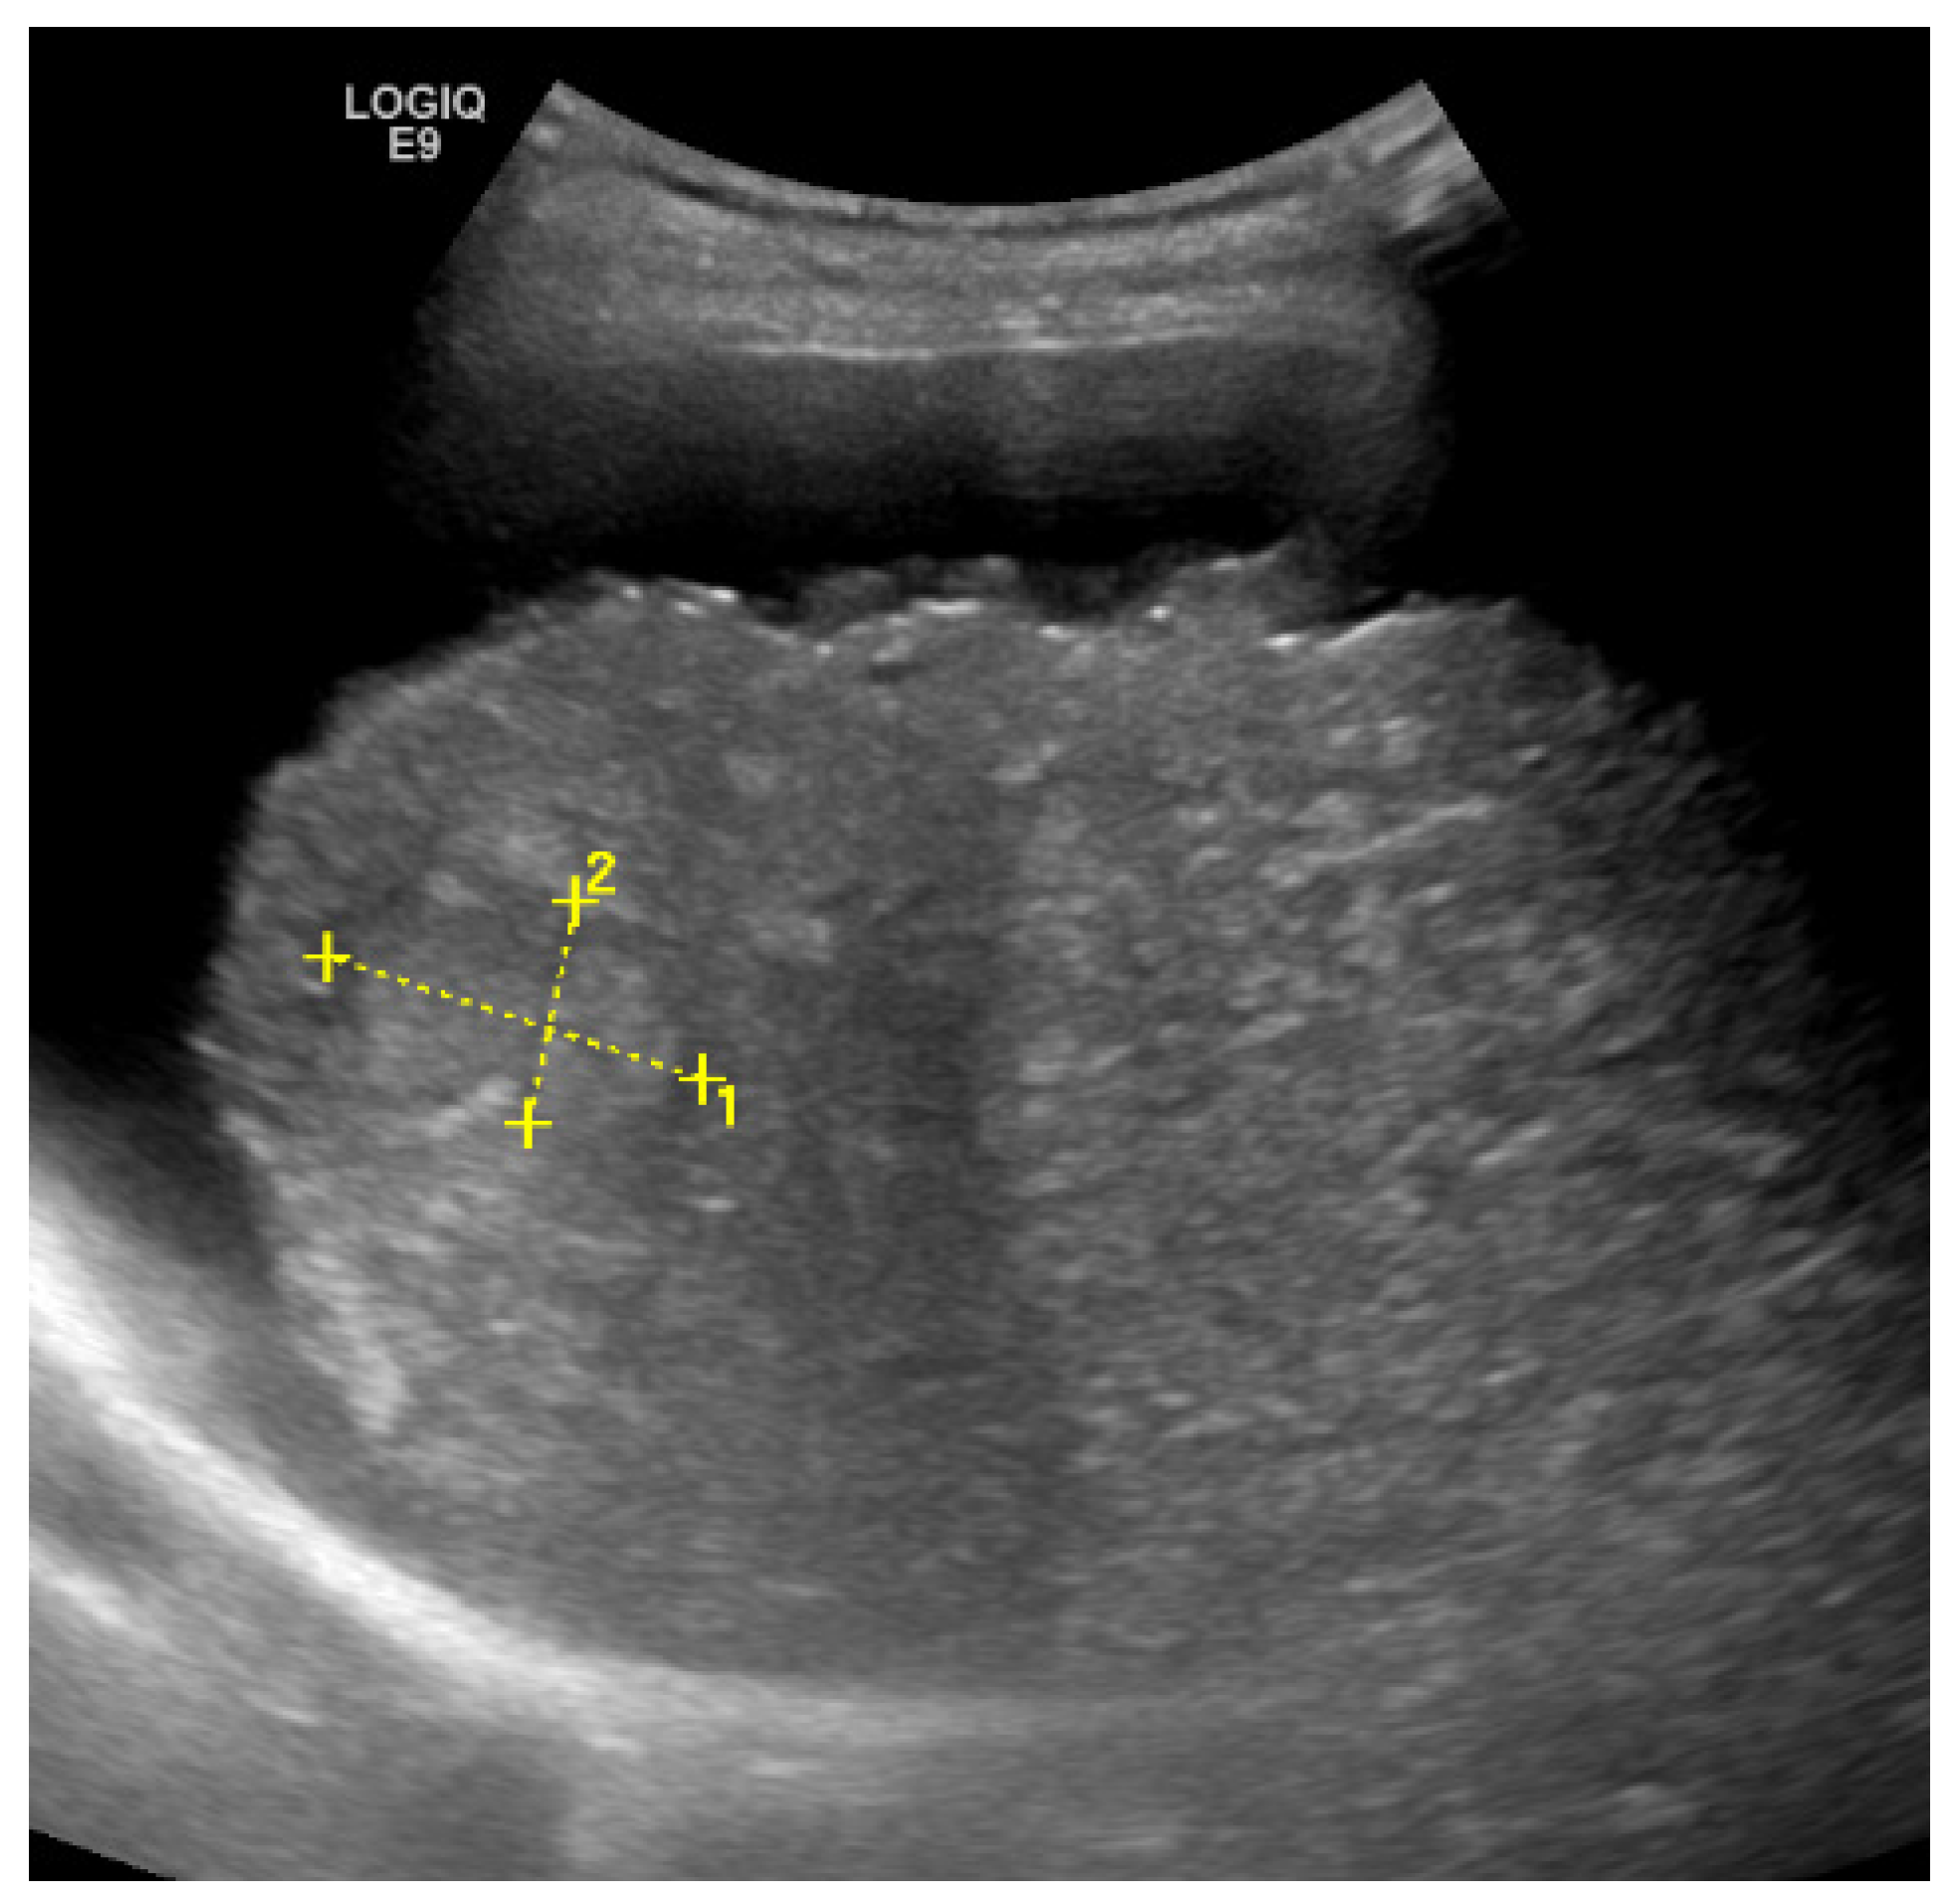

2. Detection and Graduation of Hepatic Steatosis

- Webb, M.; Yeshua, H.; Zelber-Sagi, S.; Santo, E.; Brazowski, E.; Halpern, Z.; Oren, R. Diagnostic Value of a Computerized Hepatorenal Index for Sonographic Quantification of Liver Steatosis. AJR Am. J. Roentgenol. 2009, 192, 909–914. [Google Scholar] [CrossRef] [Green Version]

- Chauhan, A.; Sultan, L.R.; Furth, E.E.; Jones, L.P.; Khungar, V.; Sehgal, C.M. Diagnostic Accuracy of Hepatorenal Index in the Detection and Grading of Hepatic Steatosis. J. Clin. Ultrasound 2016, 44, 580–586. [Google Scholar] [CrossRef] [PubMed]

- Marshall, R.H.; Eissa, M.; Bluth, E.I.; Gulotta, P.M.; Davis, N.K. Hepatorenal Index as an Accurate, Simple, and Effective Tool in Screening for Steatosis. AJR Am. J. Roentgenol. 2012, 199, 997–1002. [Google Scholar] [CrossRef]

- Wang, J.-H.; Hung, C.-H.; Kuo, F.-Y.; Eng, H.-L.; Chen, C.-H.; Lee, C.-M.; Lu, S.-N.; Hu, T.-H. Ultrasonographic Quantification of Hepatic-Renal Echogenicity Difference in Hepatic Steatosis Diagnosis. Dig. Dis. Sci. 2013, 58, 2993–3000. [Google Scholar] [CrossRef] [PubMed]

| HRI [20,21,22,23] | 62.5–100% | 54–95% | -quantitative -potentially better than US alone | -low sensitivity for mild steatosis (<30%) -additional program required to calculate HRI -lack of evidence, HRI-value depends on US device and cause of liver disease |